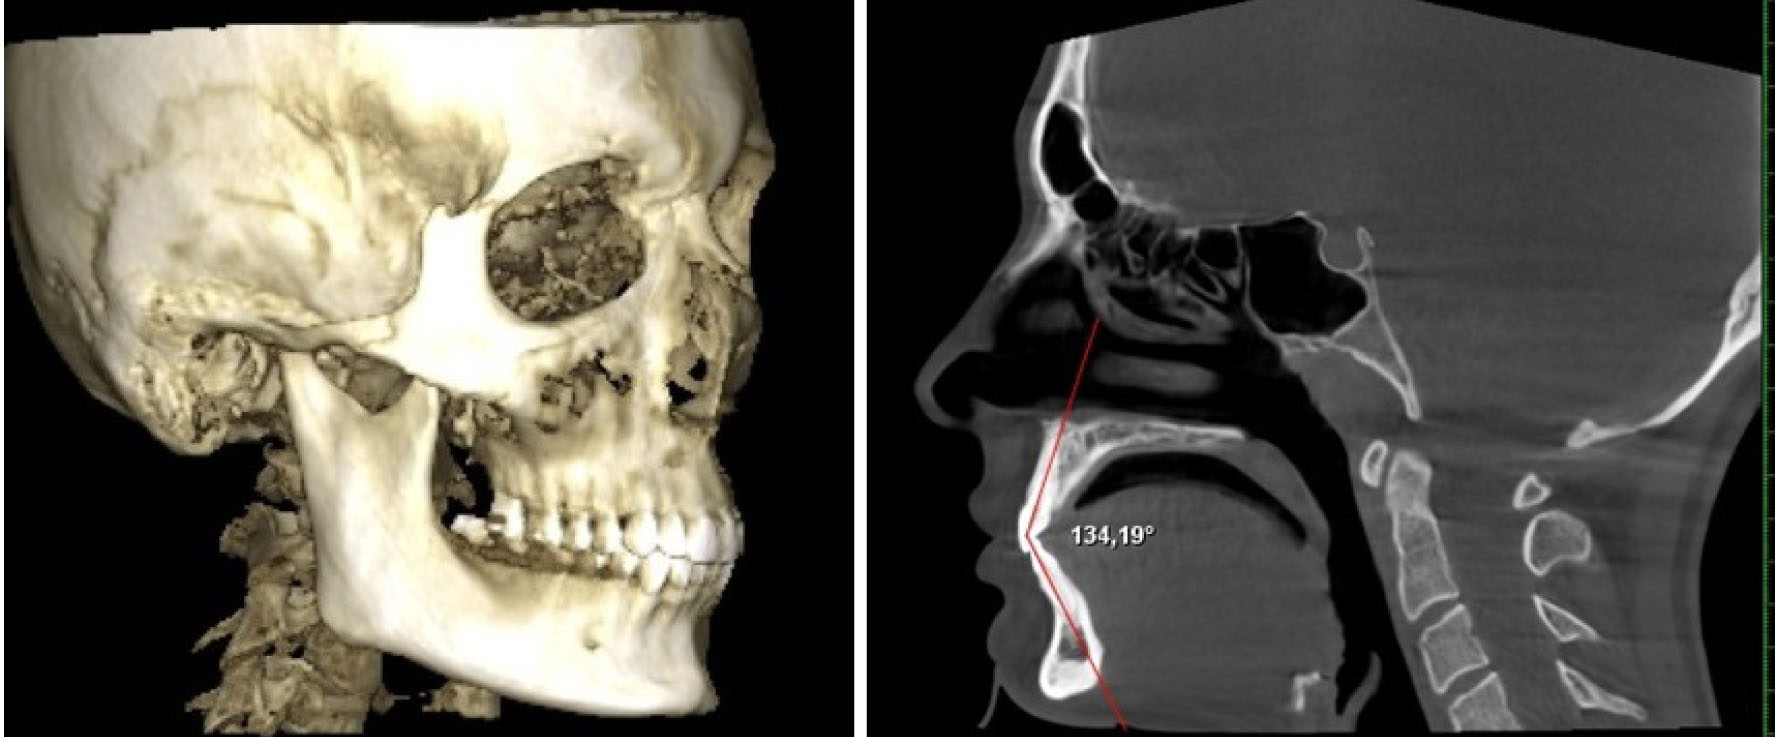

Состояние окклюзии оценивали на объемном снимке черепа, а положение передних зубов – в сагиттальной проекции (рис. 1).

Рис. 1. Объемный снимок головы и определение межрезцового угла в сагиттальной проекции

Межрезцовый угол измеряли между условными срединными вертикалями медиальных резцов, что позволяло определять трузионный тип зубо-челюстных дуг.